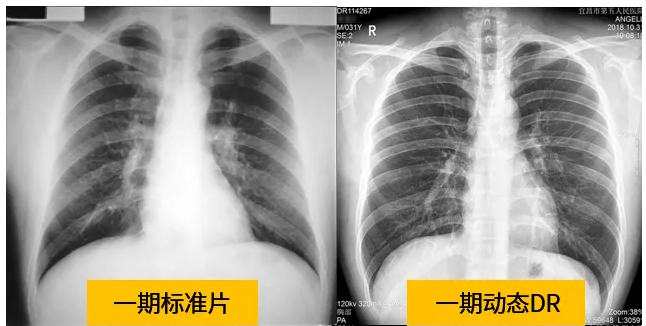

動態(tài)dr的拍攝效果圖

動態(tài)DR技術與普通DR單截面診斷的不同就是在操作過程中,可以隨時切換成透視模式,透視/攝片模式實時切換,對陰影進行多角度動態(tài)的鑒別。實時點片、實時回放、連續(xù)點片等多功能大大的增加了初診的準確率。在小陰影的形態(tài)和性質,特別是不規(guī)則小陰影的判斷方面提升,從而達到提高胸片整體判斷準確性。

根據(jù)數(shù)據(jù)統(tǒng)計表現(xiàn),利用動態(tài)dr進行檢查的話,圖像的質量和輻射劑量相對較少。并且動態(tài)DR在圖像清晰度和射線穿透力方面完全能達到塵肺診斷的要求。這種檢查效果的精準和便捷性是和普通設備不一樣的,動態(tài)DR塵肺攝影應用于塵肺疾病診斷中,可以提高檢出率及優(yōu)片率。